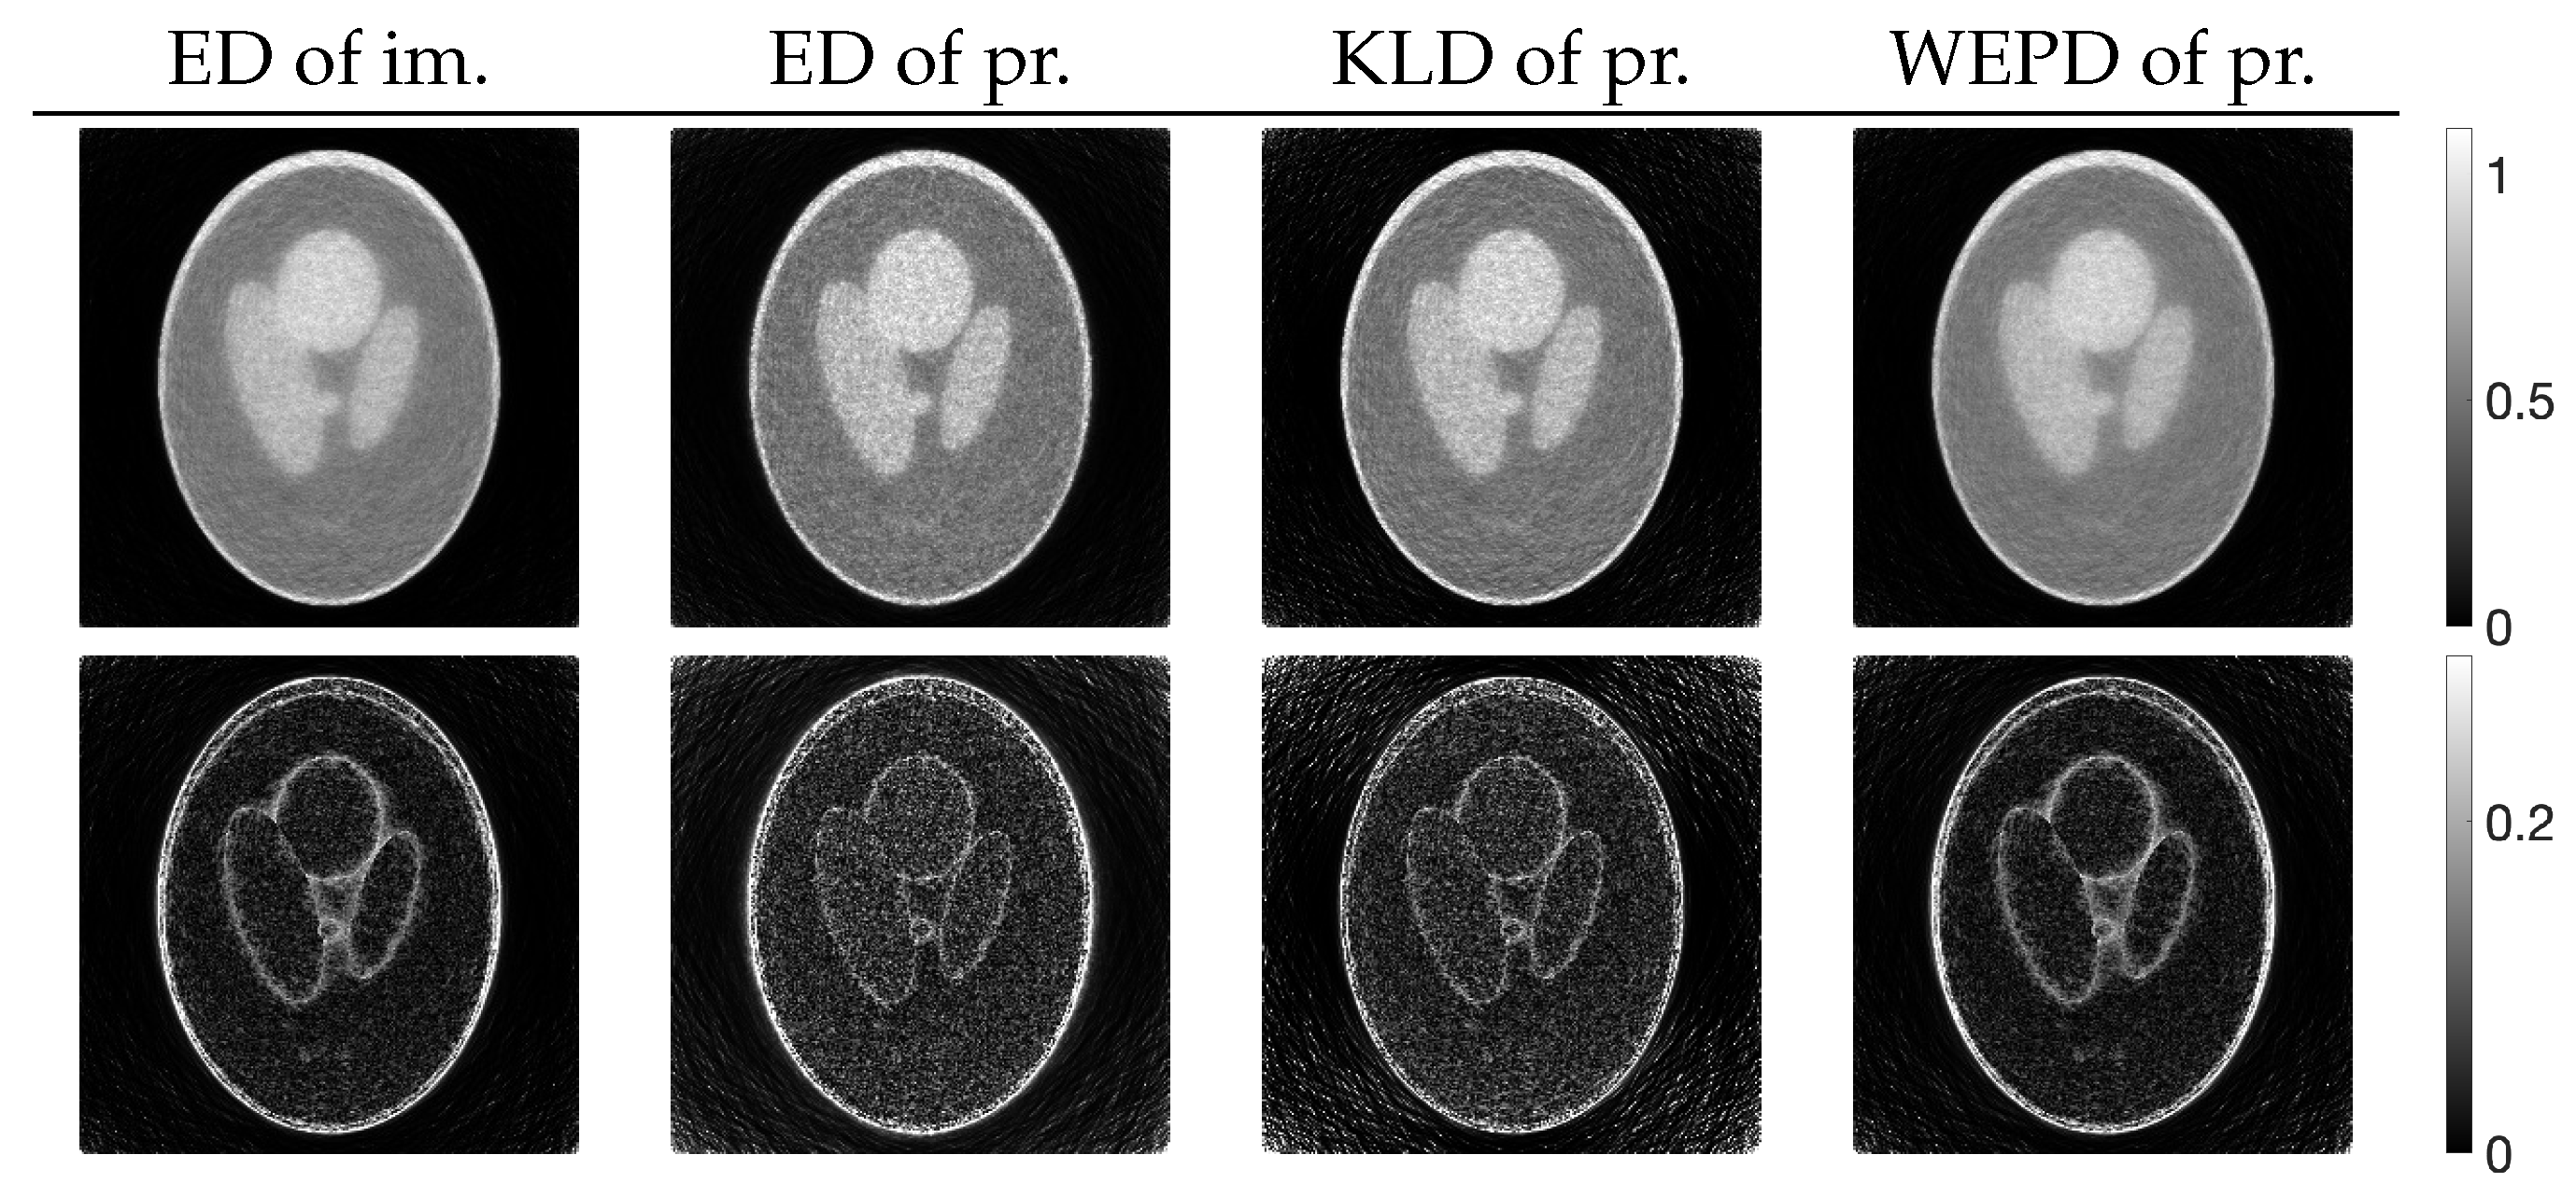

3.2. Experimental Results and Discussion

| MLEM | PDEM | PXEM | PREM | |

|---|---|---|---|---|

| std. dev. | 0.083 | 0.056 | 0.056 | 0.057 |

| contrast | 0.532 | 0.418 | 0.544 | 0.550 |